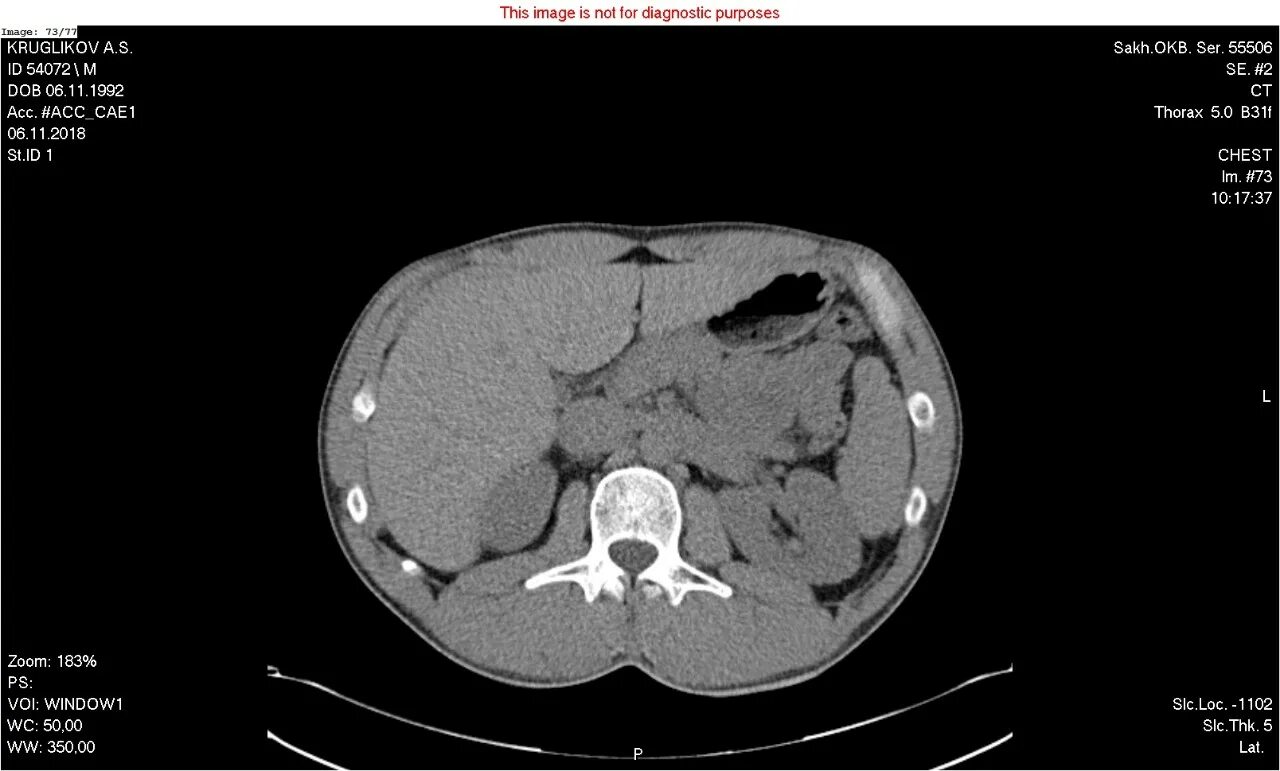

Как на кт выглядит рак